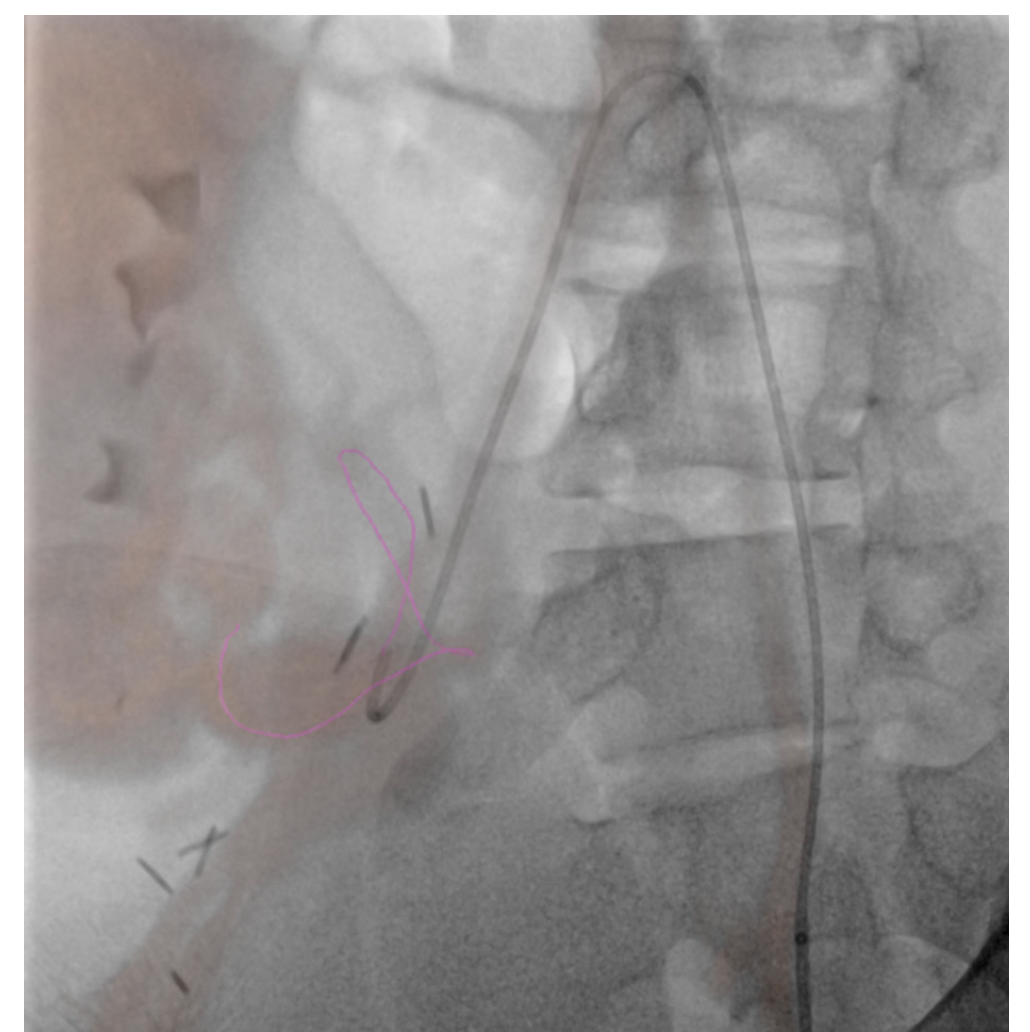

In pediatrics, MR and CT datasets are mainly used for fusion to assist with intraprocedural guidance and road mapping. As with most things in pediatrics, its use is currently limited. It is, however, an area of interest that is growing among the community. Sometimes patient vascular anatomy is complex; other times, patient size makes navigating even normal anatomy difficult. Though most interventionalists would be able to perform a complicated case without assistance, the datasets have potential to help decrease patient radiation and contrast dose in the hands of even the most skilled users. This may be able to be accomplished through use of the patient’s prior cross-sectional imaging to create 3D roadmaps on the day of treatment. While it may not be a “perfect” one-to-one recreation of the patient’s anatomy, the roadmap created and overlaid on live fluoroscopy is often more than sufficient (Figure 1). In complex cases, the roadmap created will at the very least give the interventionalist a better approximation of where a tortuous vessel’s origin might be in the 3D space (Figure 2). And if the interventionalist has a better idea of the vessel origin, they may be able to select it faster, thus limiting patient radiation and contrast dose. And while the same software can be used for even more advanced techniques such as organ segmenting, it is straightforward to use. It doesn’t matter how useful or “nifty” you think something is if it is unreliable and cumbersome to implement. Once the interventionalist understands Siemens’ simple and intuitive workflow, use of prior imaging in this manner is something that can easily be done with little effort and time. The other thing to keep in mind is with the simplified workflow; if whatever overlay was created using the patient’s prior imaging is not helpful or is a hinderance, it can easily be turned off. While it may seem counterintuitive, the ability to easily turn off an advanced feature if it is not serving its purpose is just as important as to not waste time in the suite doing unnecessary troubleshooting.

Navigational software is most useful in pediatric musculoskeletal interventions. If there is a small lesion in a difficult-to-get-to place and CT is either unavailable or unreliable, it is a wonderful tool. A safe needle trajectory can be preplanned off the original MR or CT. Once planned, it then can be fused to live fluoroscopy and the system will generate a virtual guide for the needle. By starting with a skin entry point then moving to a progression view, the needle can be safely guided down along the planned path to the area of interest. I place a high value on having a plan B or C if your original plan is not working. Siemens needle guidance software accomplishes just that. If the plan made from the patient’s original imaging is not working, the case can be easily troubleshot with syngo DynaCT. A syngo DynaCT can be performed, and a new trajectory can be planned so the case can continue. Troubleshooting with syngo DynaCT is made even easier with the new ARTIS icono. The technology allows for speedy acquisition at a reasonably low dose so if the original plan isn’t working, abandoning it and starting over with syngo DynaCT so that the case can safely be performed is a more palatable option.